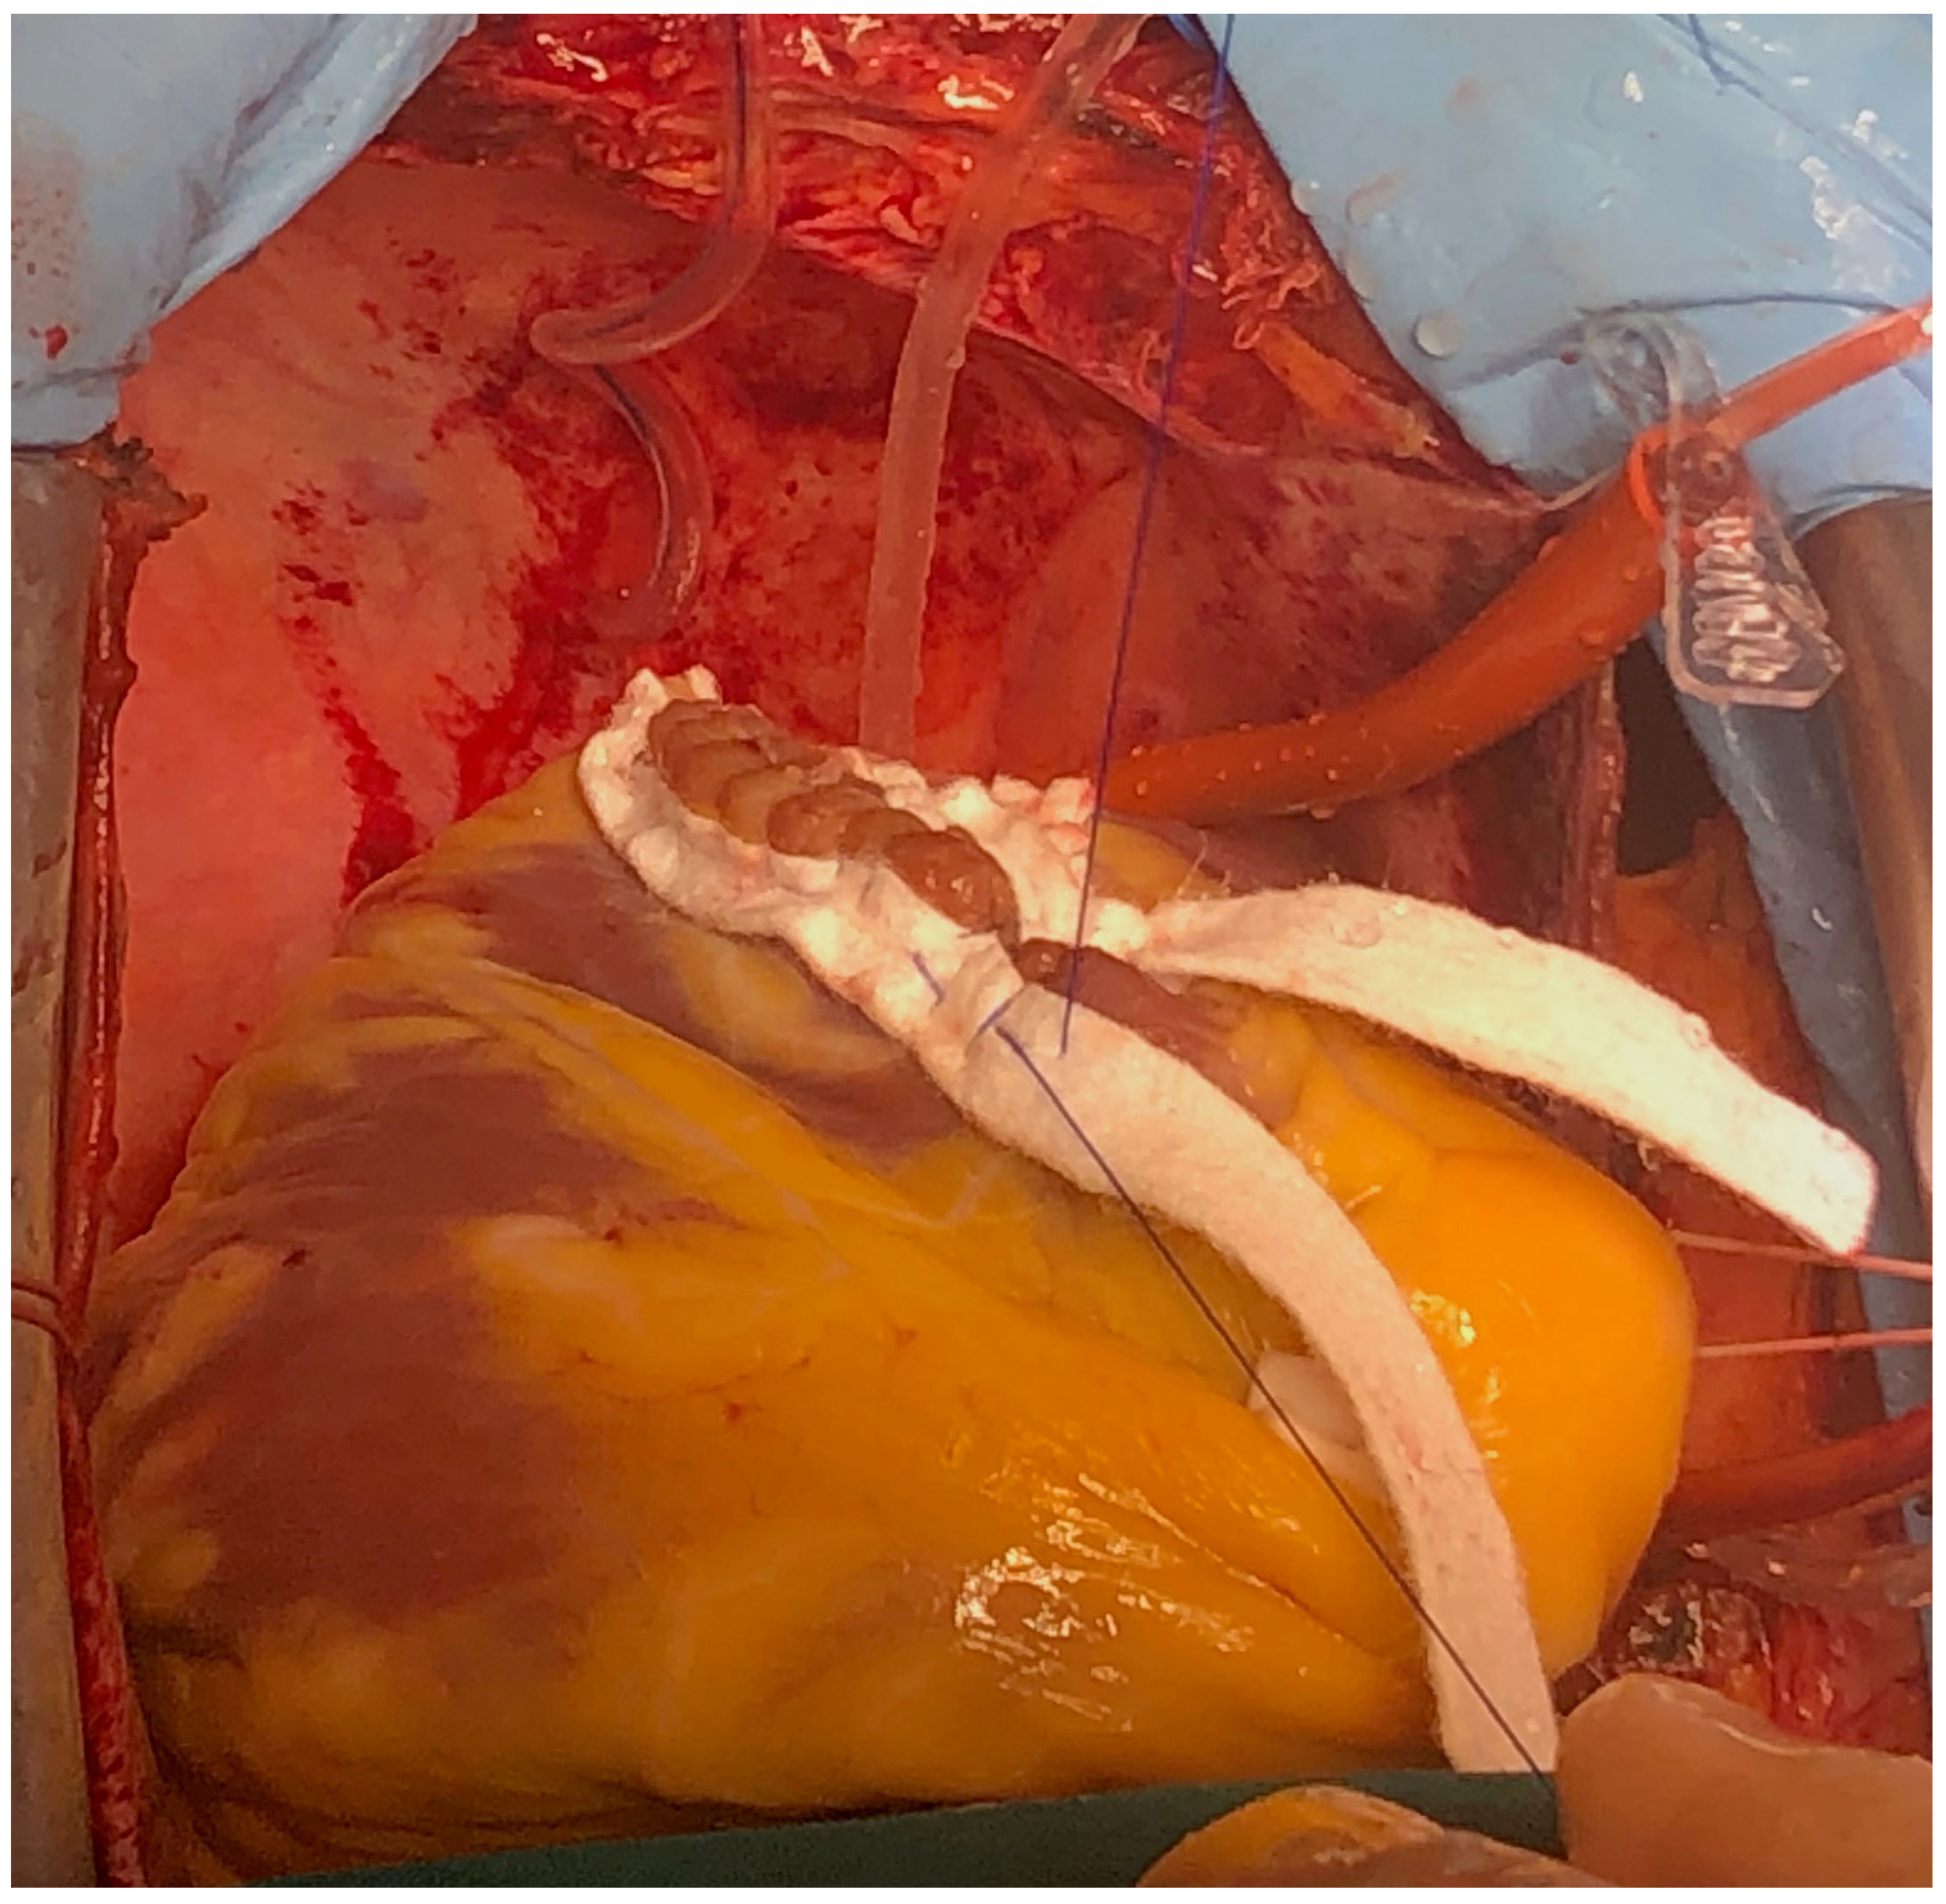

The case was discussed in the multidisciplinary heart team (cardiologist, interventional cardiologist, cardiac surgeon, anesthesiologist) and, after informed consent, it was decided for a watchful waiting tactic, planning a delayed repair. Preoperatively, the patient was evaluated with a transesophageal echocardiography (TEE) for better defect characterization and MR quantification (Figure 3 and Figure 4). Percutaneous defect closure was deemed technically unfeasible due to the anatomy of the defect, which was located at the base of the septum and involved the mitral valve apparatus, while also exhibiting significant mitral valve regurgitation.

The surgery was carried out under general anesthesia, with iv induction and inhaled sevoflurane maintenance and total iv anesthesia during CPB. After median sternotomy, bicaval CPB was started, and the heart was arrested using anterograde and retrograde cold blood cardioplegia. After snaring both venae cava, the heart was enucleated with a 3.0 polypropylene stitch at the apex. A 10 cm incision was made on the posterior surface of the left ventricle, 2 mm parallel to the posterior interventricular artery. The margins of the VSD were identified. Interrupted matrass sutures of 2.0 Tevdek were placed circumferentially around the defect and used to secure a 4 × 7 cm bovine pericardial patch. The posterior papillary muscle was retracted into the sutures, so the mitral valve was replaced with a 27 biological prosthesis with preservation of the sub-valvular apparatus. The left ventriculotomy was closed with a double layer surjet suture, reinforced with Teflon felts. Details with surgical technique are shown in Figure 5, Figure 6, Figure 7 and Figure 8.

Figure 5. Surgical technique detail—exposure of VSD.